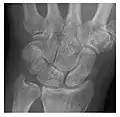

Occult osseous injuries may result from a direct blow to the bone by compressive forces of adjacent bones against one another or by traction forces during an avulsion injury. Lesions in the tibial plateau, hip, ankle, and wrist are often missed. In a tibial plateau fracture, any disruption of the posterior and anterior cortical rims of the plateau should be sought. Impaction of subchondral bone will appear as an increased sclerosis of the subchondral bone (Figure 1). In the hip, posterior acetabular fractures also present subtle radiographic findings. The acetabular lines should then be carefully examined keeping in mind that the posterior rim, which is harder to see on X-rays, is more frequently fractured than the anterior rim (Figure 2). In the wrist, detection of carpal bone fractures is often challenging, with up to 18% of scaphoid fractures radiographically occult. Carpal fractures, especially the scaphoid, are associated with the risk of avascular necrosis. In apparently normal wrist radiographs from symptomatic patients, if there is history of a fall on an outstretched hand with pain in the anatomic snuffbox, suggesting scaphoid injury, the initial examination with posteroanterior, lateral, and pronation oblique views must be complemented by other specific views such as supination oblique and the "scaphoid" view A careful examination of cortices for evidence of discontinuity or offset and cancellous bone for lucency is necessary (Figure 3).[1]

Figure 3: A 26-year-old man presenting with wrist pain after being assaulted. (a) Initial anteroposterior radiograph shows a subtle linear lucency within the scaphoid extending to the scaphocapitate articular surface that was overlooked (arrow). (b) Initial "scaphoid" view was negative. (c) Followup anteroposterior radiographs, 12 days later, shows obvious scaphoid fracture (arrows).[1]